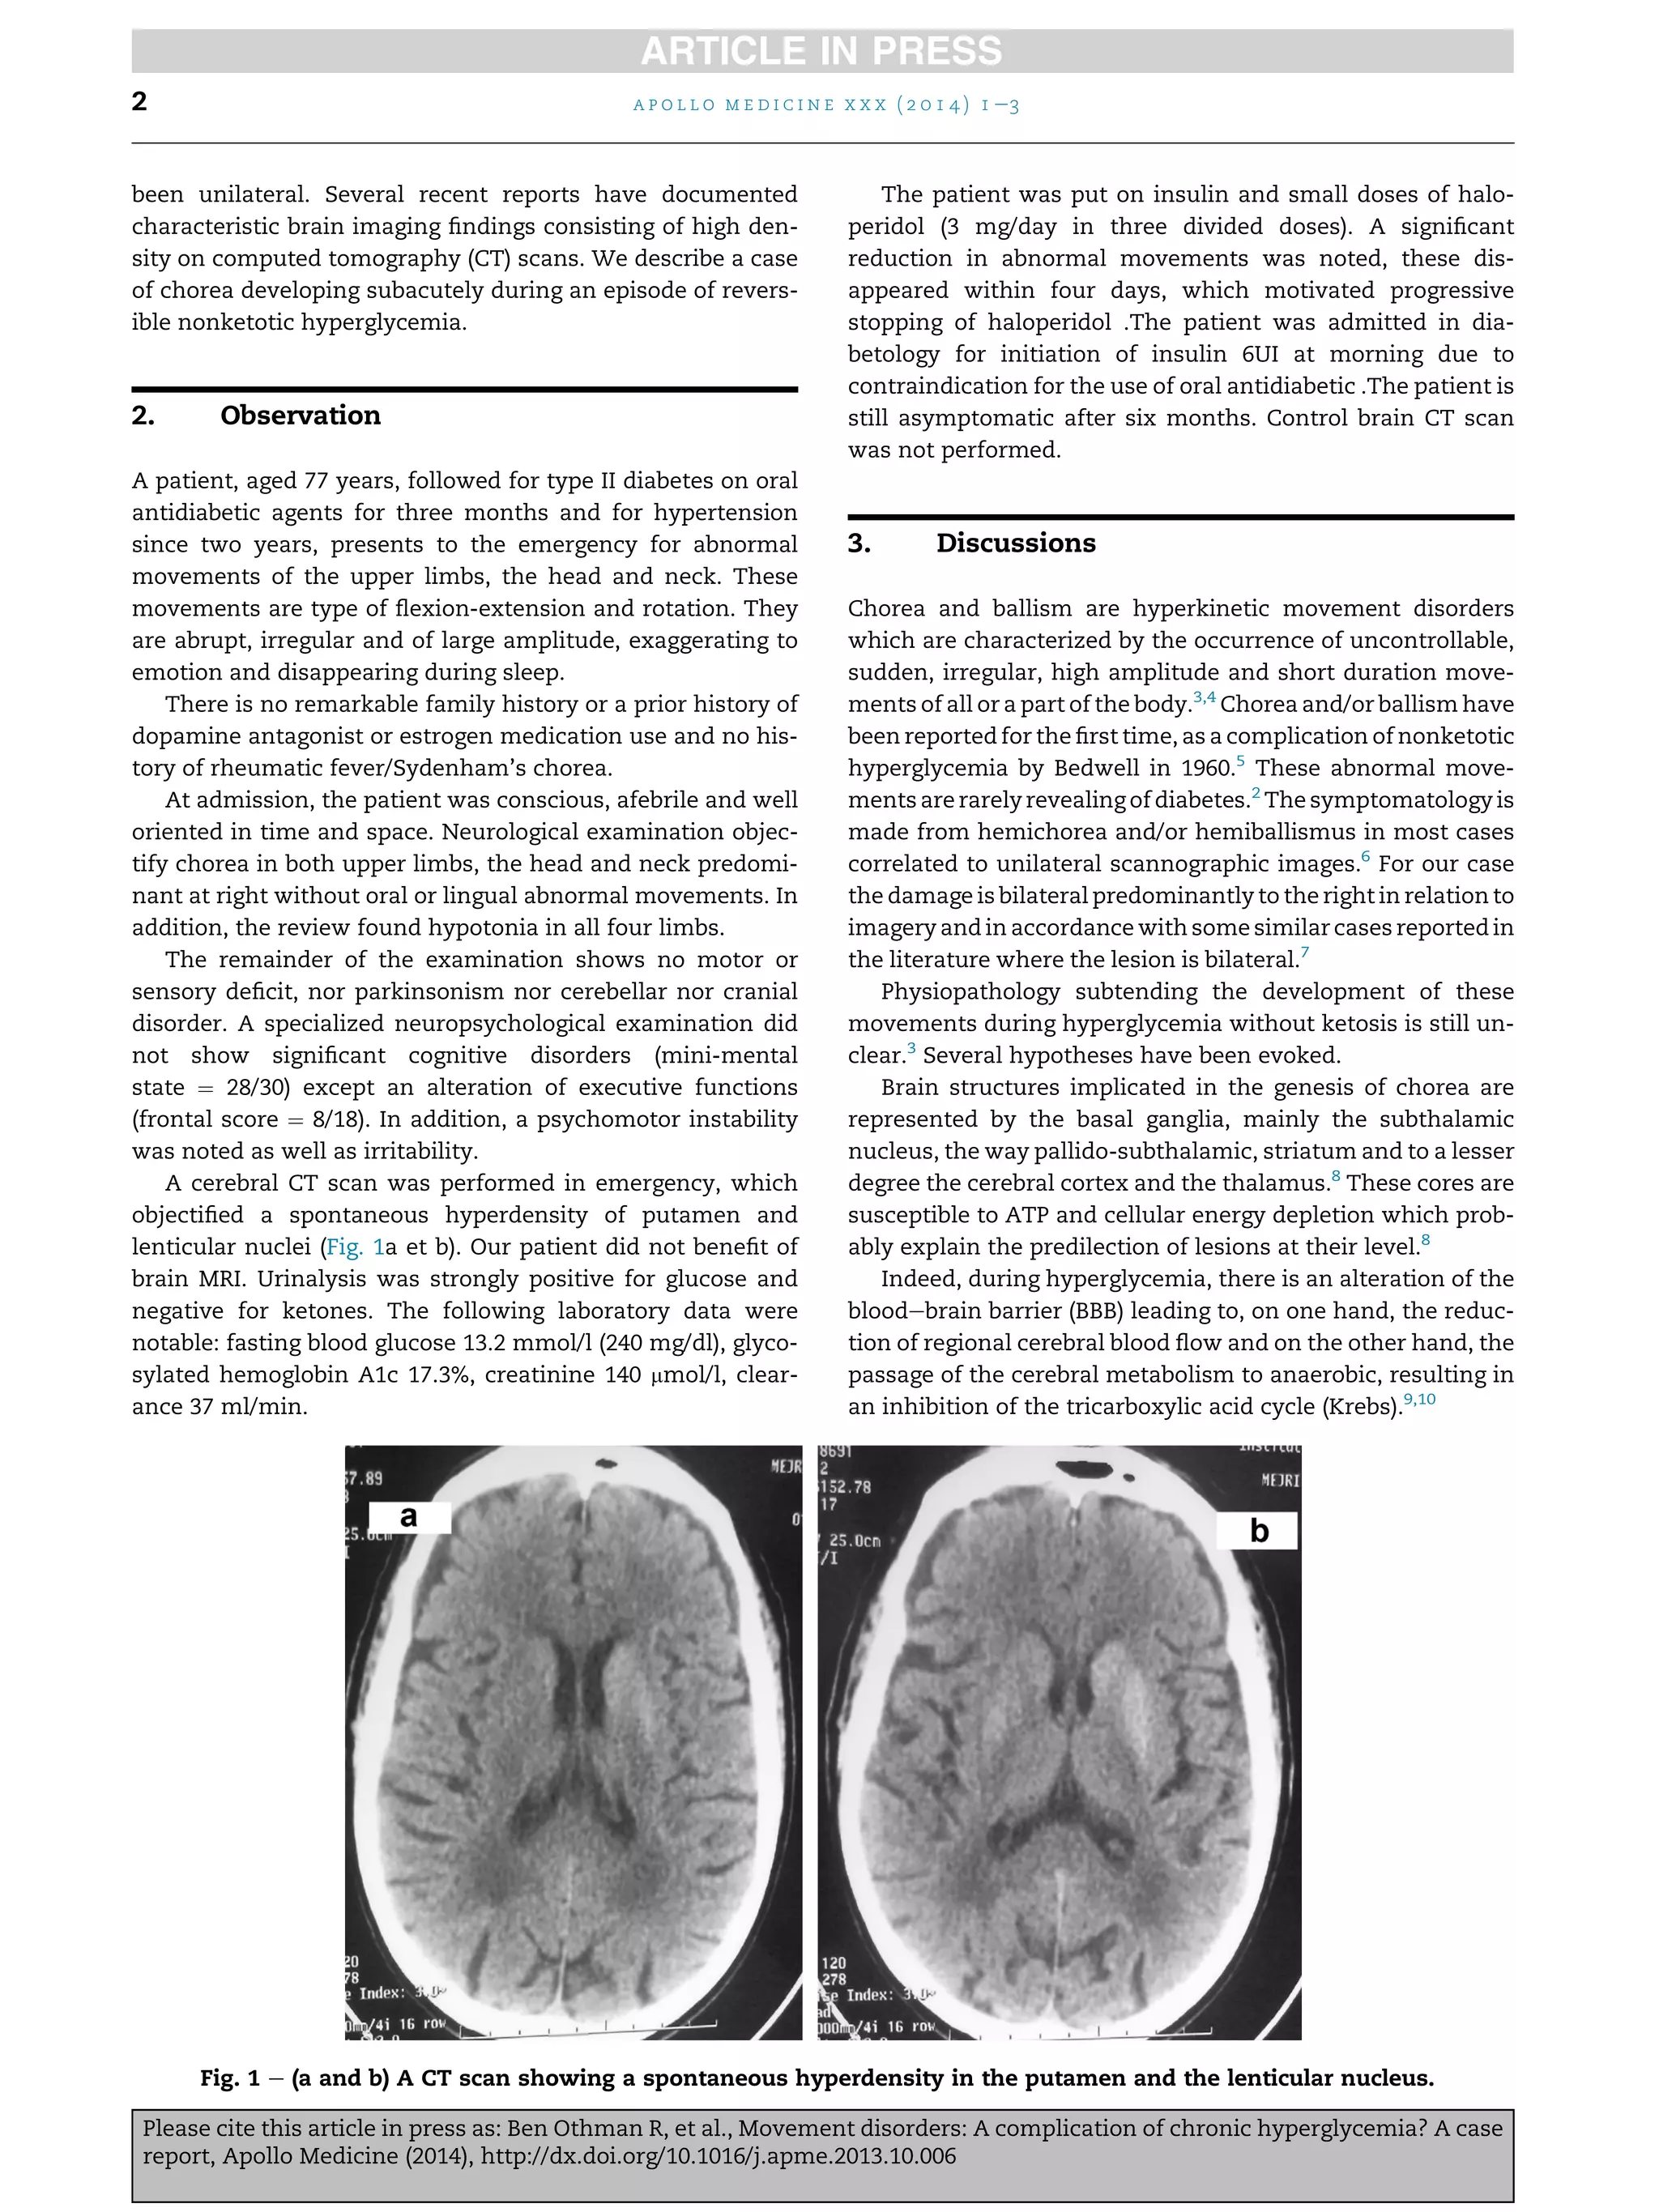

A cerebral CT scan was performed in emergency, which

objectified a spontaneous hyperdensity of putamen and

lenticular nuclei (Fig. 1a et b). Our patient did not benefit of

Fig. 1 e (a and b) A CT scan showing a spontaneous hyperdensity in the putamen and the lenticular nucleus.